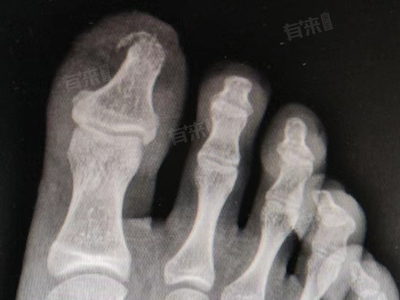

- 脚趾轻微骨裂是一种常见的足部损伤,其愈合过程是一个复杂且受多种因素影响的生物学过程。骨裂发生后,人体会启动一系列修复机制,包括骨折端血肿形成、纤维骨痂形成、骨性骨痂形成及骨痂改造塑形等阶段,上述阶段的进展速度,直接决定了骨裂愈合所需的时间。

- 从生理角度来看,不同年龄段人群的脚趾轻微骨裂愈合时间存在显著差异,儿童处于生长发育阶段,骨骼代谢旺盛,成骨细胞活跃,其脚趾轻微骨裂后的愈合速度较快。通常在骨裂后的2-3周,血肿开始机化形成纤维性骨痂,4-6周就能形成较为稳定的骨性骨痂,基本实现临床愈合,即骨折部位初步稳定,疼痛和肿胀明显减轻。

- 青少年的骨骼发育虽已接近成熟,但仍具备较强的修复能力。在骨裂发生后的3-4周,纤维骨痂逐渐向骨性骨痂转化,6-8周时骨性骨痂不断生长、加固,达到临床愈合状态。但此时骨骼的强度尚未完全恢复到受伤前水平,仍需一段时间进行骨痂改造塑形。

- 对于成年人而言,身体新陈代谢速度趋于稳定,骨组织的修复能力相对青少年有所下降。脚趾轻微骨裂后,骨折部位的修复进程相对缓慢。一般在受伤后的4-5周,才能初步形成骨性骨痂,8-10周达到临床愈合标准。之后还需要持续数月的时间,让新生的骨组织不断重塑,恢复骨骼的正常结构和功能。

此外,骨裂的具体部位也会对愈合时间产生影响,大脚趾承担着人体行走和站立时较大的压力,其轻微骨裂后,由于活动频繁,骨折端易受到外力干扰,愈合时间通常比其他脚趾稍长。而小脚趾相对活动度较小,受到的应力较小,愈合时间可能相对短一些。